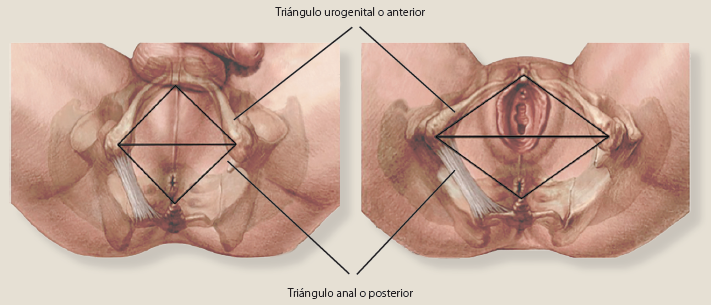

La gangrena de Fournier se origina en uno de los 2 triángulos del periné, desde el triángulo anal o posterior, o desde el triángulo urogenital o anterior (figura 3); la infección originada en el triángulo posterior se propaga a través de la fascia de Colles, y si se origina en el triángulo urogenital se propagará a través de la fascia de Buck, posteriormente se ve involucrada la fascia dartos, y si se compromete la fascia de Scarpa, la infección podría extenderse a la pared abdominal anterior7. La fascitis necrotizante produce trombosis de la microcirculación subcutánea, con progresión de la gangrena. Se ha reportado que la tasa de progresión de la necrosis puede alcanzar de 2 a 3 cm por hora2.